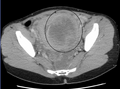

A very large (9 cm) fibroid of the uterus which is causing pelvic congestion syndrome as seen on CT

A very large (9 cm) fibroid of the uterus which is causing pelvic congestion syndrome as seen on ultrasound

A small uterine fibroid seen within the wall of the myometrium on a cross-sectional ultrasound view